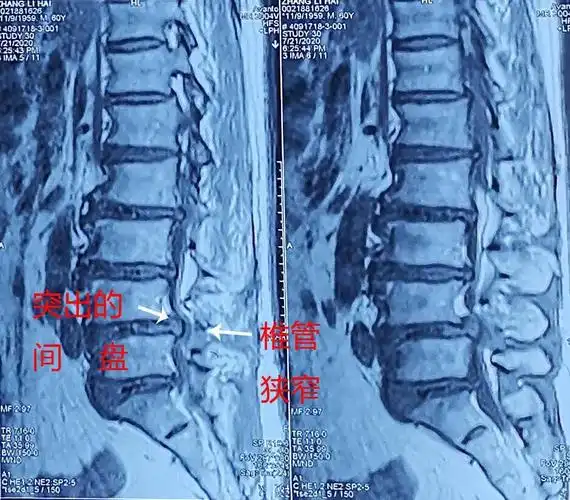

经肌间隙入路微创通道手术治疗腰椎管狭窄和腰间盘突出_腰椎管狭窄